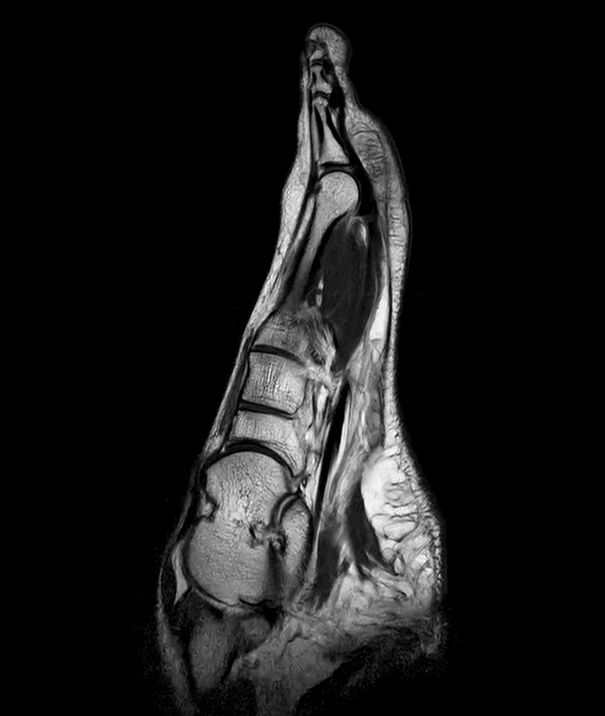

Sagittal T1w TSE